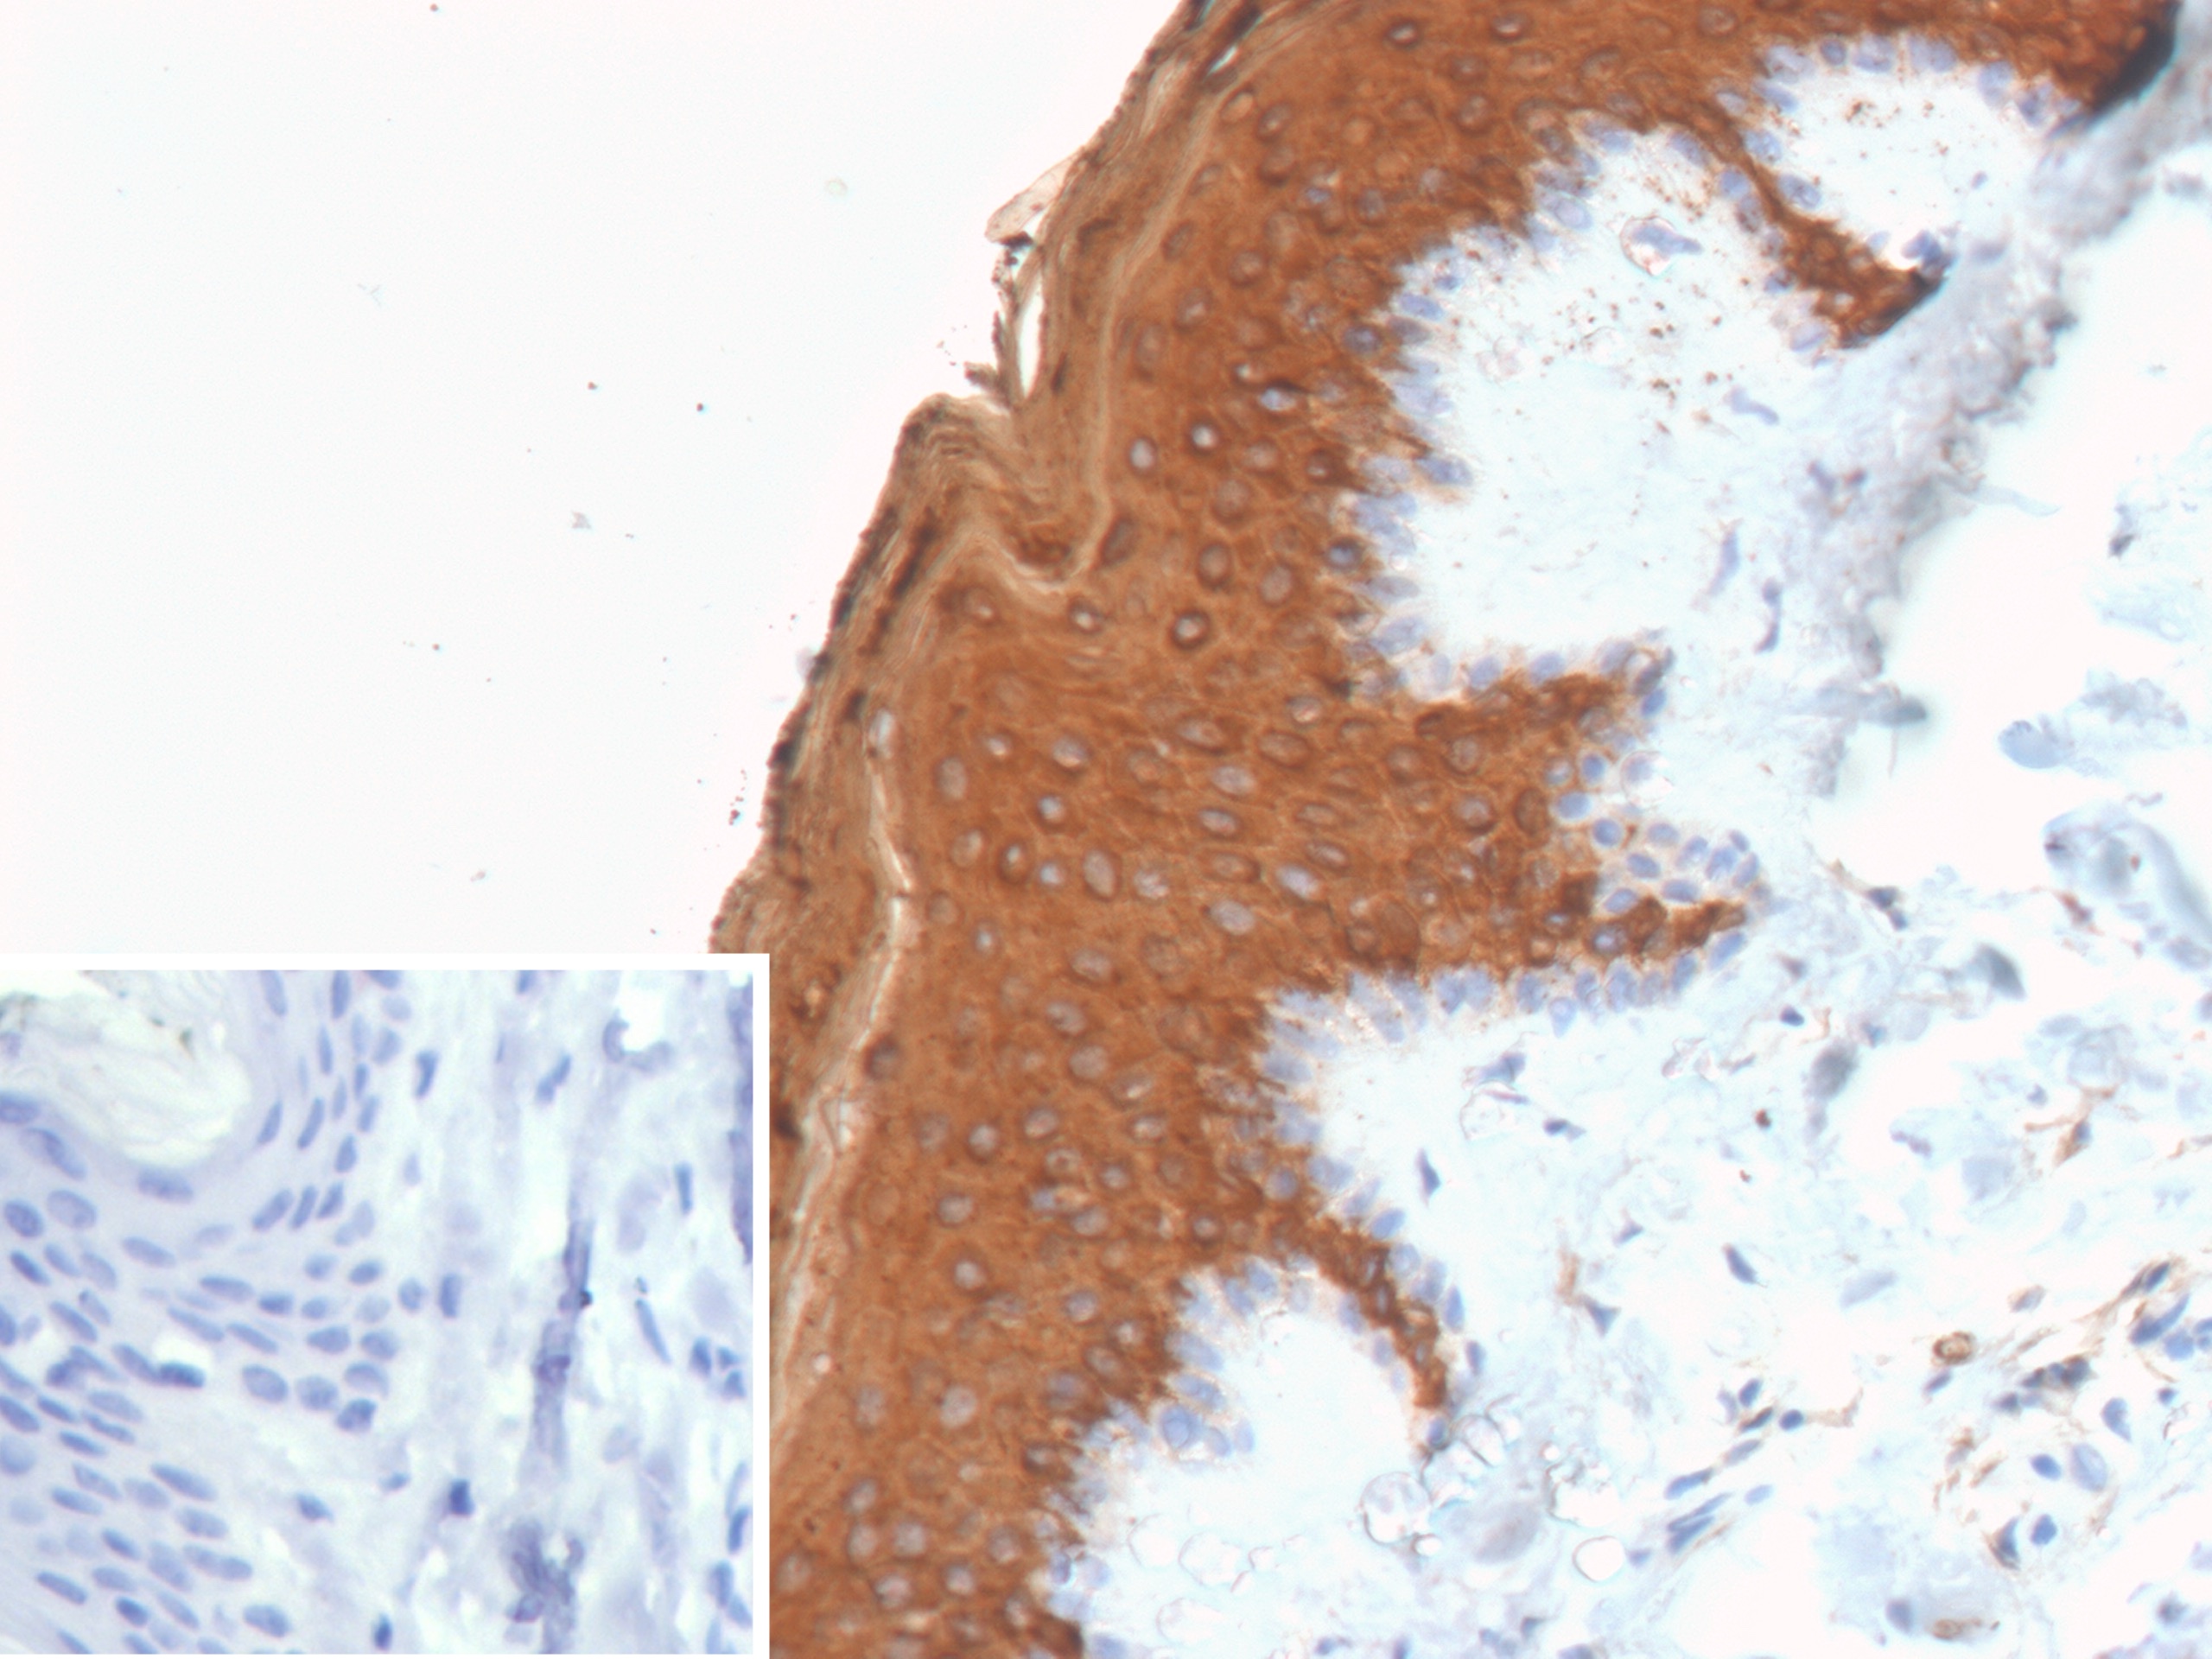

Formalin-fixed, paraffin-embedded human skin stained with Cytokeratin 10 Recombinant Rabbit Monoclonal Antibody (KRT10/9605R). Inset: PBS instead of primary antibody; secondary only negative control.

This MAb recognizes a protein of 56.5kDa, identified as cytokeratin 10 (CK10). CK10 is expressed in all suprabasal layers of the epidermis. In the epidermis, expression of CK10 strictly parallels the extent of differentiation; it is absent in the basal layer, appears in the first suprabasal layers and increases in concentration towards the granular layer. However, CK10 is rarely detected in early stages of vulvar squamous carcinomas (tumors less than 2 cm, clinical stage I) regardless of the tumor grade. In larger and more advanced tumors (greater than 2 cm, clinical stages II and III), CK10 is detected very frequently. Expression of CK10 is related to maturation of malignant keratinocytes, being preferentially detected in more-differentiated parts.